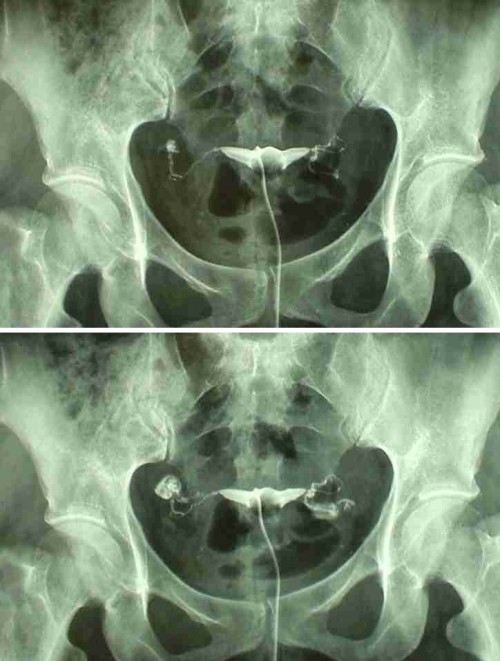

Гистеросальпингография: описание и фотографии